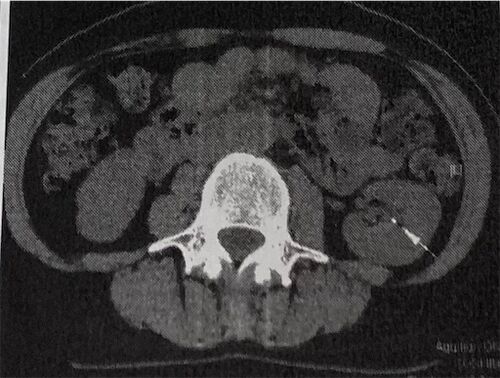

あなたは体の中に石を何個持っていますか?

私は最低2つは持っています! 右側と左側の腎臓に最低ひとつずつです。 わ〜〜〜い、わ〜〜い! じゃないわ・・・( ̄▽ ̄)/ お腹の中に石ころがあって良いことなんて一つもないし! 5、6年前から左右の腎臓に石があることはわかっていましたが、そいつがと…